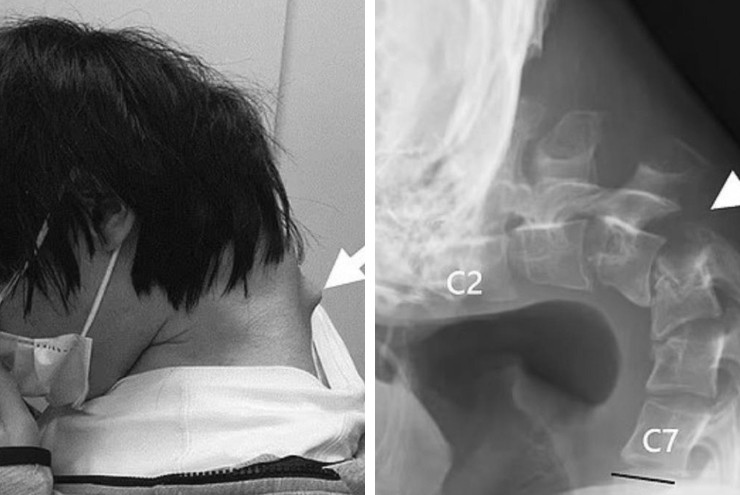

Kết quả là cổ của anh dần gập lại thành một góc gần 90 độ, xuất hiện một khối lạ nhô ra. Tình trạng này khiến việc nuốt nước bọt trở thành một cơn ác mộng.

Khi đến bệnh viện, các bác sĩ rất bất ngờ trước tình trạng của bệnh nhân. Hình ảnh X-quang cho thấy cổ của anh gần như gập song song với ngực, với các đốt sống bị biến dạng nghiêm trọng. Bệnh nhân không thể tự nâng cổ, phải dùng tay đỡ khi di chuyển.